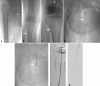

The treatment of chronic total occlusions (CTO) in patients with peripheral arterial disease (PAD) is a complex topic with multiple treatment techniques and treatment strategies. The interventionalist treating patients with PAD should have both a defined treatment algorithm and multiple techniques available for crossing these challenging lesions. This article will cover techniques for treating CTOs and provide an overview of current available evidence.